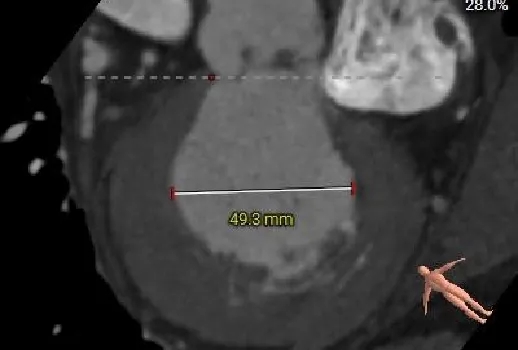

三叶式主动脉瓣,微量钙化,瓣叶增厚;瓣环周长折算直径26.6mm,LVOT29.3mm。

左室增大,瓣环夹角54°,非横位心。

LVOT:29.3mm

瓣上2mm:25.2mm

瓣上4mm:25.4mm

瓣上6mm:26.6mm

瓣上8mm:27.5mm